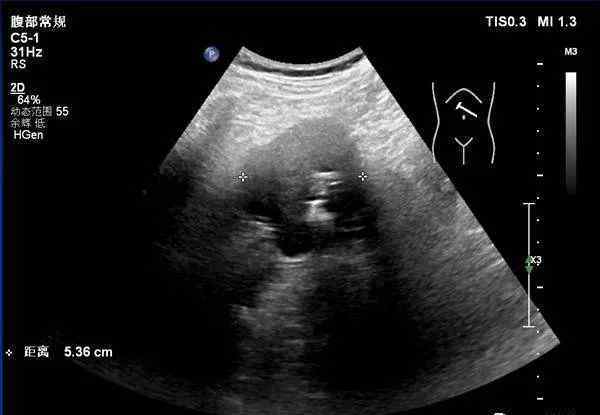

饮用500毫升水后,在左上胃体前壁可见大小约64毫米×54毫米×49毫米的低回声团块,边界清楚,突出于胃腔外,内部呈条状强回声,CDFI无明显血流信号。超声造影:经肘静脉团注2.4毫升硝酸甘油后,病变动脉期与胃壁同步增强,消退期快于胃壁。

1.左上胃前壁被低回声占据,超声造影后可考虑胃间质瘤。